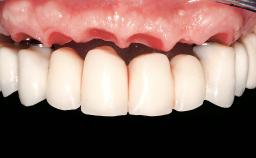

Conventional Loading of Eight Implants in the Maxilla and Final Restoration with a Full-Arch Gold-Ceramic FDP

Prosthesis Type FDP

Defining Characteristics Fully edentulous upper jaw to be rehabilitated with an implant-borne fixed dental prosthesis

Loading Protocol Conventional or early